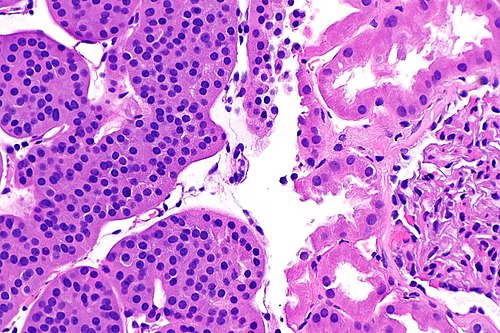

2

Diagnosis?

Wilms tumour - high mag.jpg

Angiomyolipoma

Benign kidney

Chromophobe renal cell carcinoma (classic)

Chromophobe renal cell carcinoma (eosinophilic)

Clear cell papillary renal cell carcinoma

Clear cell renal cell carcinoma

Collecting duct carcinoma

Cystic nephroma/mixed epithelial stromal tumour

HLRCC syndrome associated RCC

Hybrid oncocytic/chromophobe tumour

Metastatic carcinoma

Mucinous tubular and spindle cell carcinoma

Oncocytoma

Papillary renal cell carcinoma

Renal cell carcinoma, unclassified

Renal medullary carcinoma

Succinate dehydrogenase-deficient renal cell carcinoma

t(6;11) translocation carcinoma

Tubulocystic renal cell carcinoma

Urothelial carcinoma

Wilms tumour

Xanthogranulomatous pyelonephritis

Xp11.2 translocation carcinoma